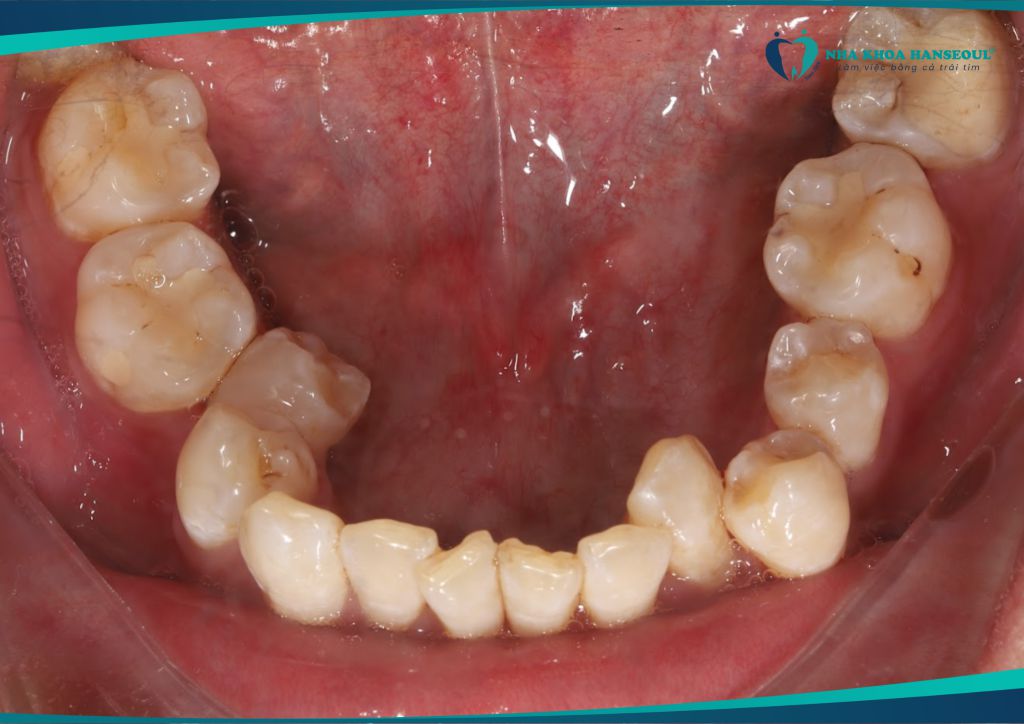

Anh Trường gặp phải tình trạng khớp cắn ngược hạng III móm. Đây là một dạng sai khớp cắn khiến hàm dưới đưa ra trước. Ảnh hưởng đến cả chức năng ăn nhai lẫn thẩm mỹ khuôn mặt. Ngoài ra, anh còn gặp tình trạng răng khôn sâu, thường xuyên đau nhức. Ảnh hưởng lớn đến sinh hoạt hằng ngày.

Anh Trường đến với Nha khoa Hanseoul và được bác sĩ chuyên môn thăm khám, tư vấn kỹ lưỡng. Anh quyết định nhổ răng khôn, tiến hành niềng răng trong suốt Invisalign để cải thiện toàn diện tình trạng răng miệng.